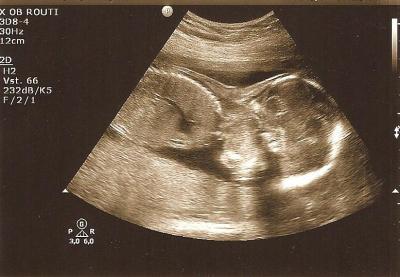

huhu ihr lieben, es ist soweit, wird haben ein outing, es wird gaaaaaanz eindeutig ein JUNGE alles drin, alles dran, alles im grünen bereich!!!! lustig ist, dass der kleine mit dem köpfchen richtung blase liegt, also liegt er immer auf der nase der arzt musste selbst grinsen, wie süße er liegt! waren eben jungenbodys kaufen, mit herz und seele!!!! das wollt ich mir heut wirklich gönnen!!! schicke euch bilder, hoffe es klappt! LG Marta 20+5

ein beinchen, das nach unten zeigt

und links DAS GANZ EINDEUTIGE ZEICHEN, ein SCHNIEDEL